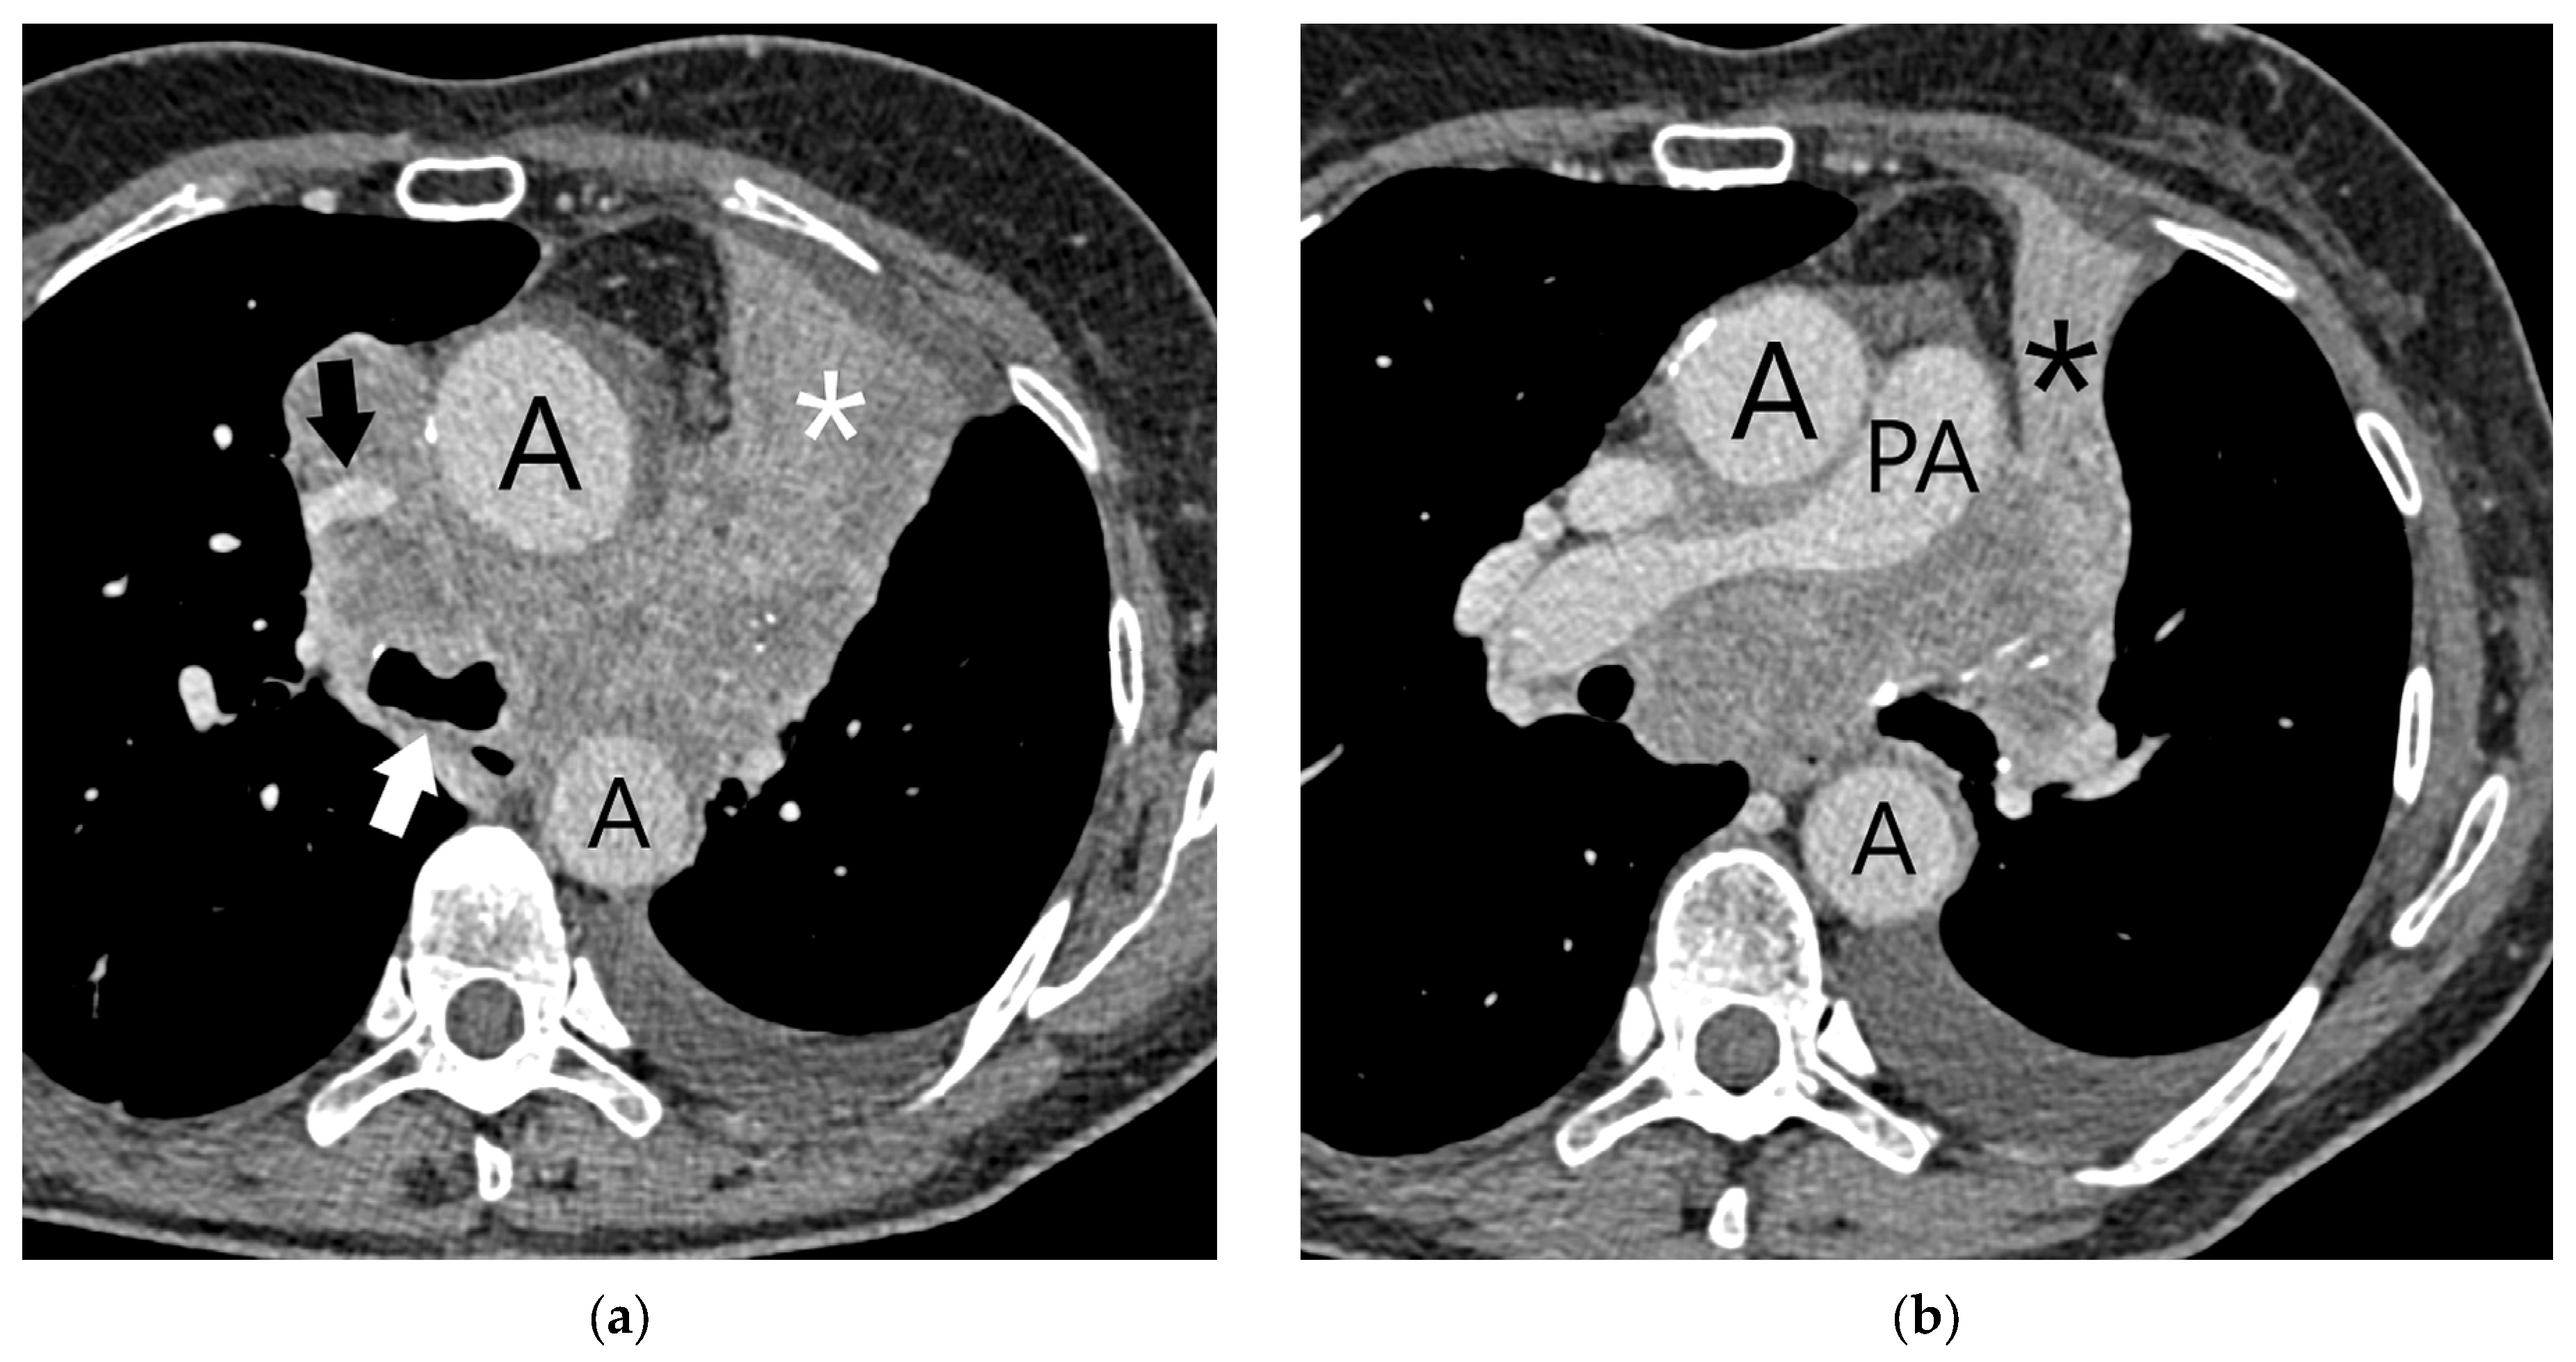

| T4 | Tumor > 7 cm in the greatest dimension Invasion of the mediastinum, thymus, trachea, carina, recurrent laryngeal nerve, vagus nerve, esophagus, or diaphragm Invasion of the heart, great vessels (aorta, superior or inferior vena cava, intrapericardial pulmonary arteries or veins), supra-aortic arteries, or brachiocephalic veins Invasion of subclavian vessels, vertebral body, lamina, spinal canal, cervical nerve roots, or brachial plexus Separate tumor nodule(s) in a different ipsilateral lobe than that of the primary | Signs of mediastinal invasion: infiltration of the mediastinal fat or structures that indicate the T4 stage, tumor–mediastinum contact length of more than 3 cm, an obtuse angle between the tumor and the mediastinum [37] Signs of vascular invasion: disappearance of the fat layer between the mass and the vessel, the angle between the mass and vessel wall >90°, a stenosis or deformation of the vascular lumen [41,42] |